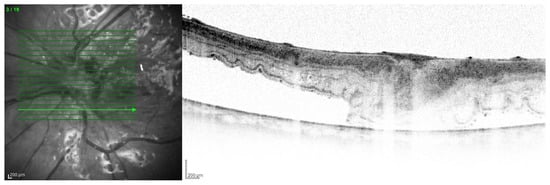

The tendency to abscess formation in the course of Klebsiella infection is also reflected in eye. One of the rare but characteristic feature of EE in the course of Klebsiella infection is the formation of subretinal abscesses [26]. They take the form of retinal elevation and paleness (Figure 1 and Figure 2). With properly selected antibiotic therapy, even large abscesses may be absorbed. If the patient is undergoing vitrectomy, intraoperative drainage may be considered [27].

Figure 1.

Fundus pictures of subretinal abscess, taken on the second day after vitrectomy. Partially drained abscess is visible, located nasally from the optic disc. Poor image quality is caused by the presence of inflammatory cells in the anterior chamber.

The main problem in patients after endophthalmitis is the damage to the retina, especially atrophy and remodeling of retinal layers, which disrupts its function and worsening visual acuity [89]. Changes can be very accurately imaged in optical coherence tomography (Figure 13). In addition, dysfunction of the pigment epithelium and abnormalities of the blood–retinal barrier can lead to persistent macular edema (Figure 14).

Figure 13.

OCT scan with extensive structural changes in the retina. Visible atrophic changes, the remodeling of the layers of the retina, and intraretinal edema in the temporal part.